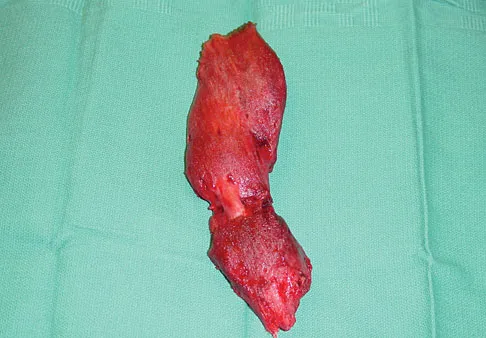

A 38-year-old left hand-dominant bodybuilder reports ecchymosis in the left axilla and anterior brachium after sustaining an injury while bench pressing 3 weeks ago. Coronal and axial MRI scans are shown in Figures 16a and 16b. What treatment method yields the best long-term results?

Explanation